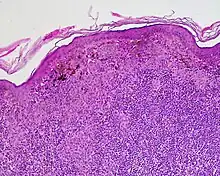

Halo nevus (also known as "Leukoderma acquisitum centrifugum," "Perinevoid vitiligo," and "Sutton nevus"[1]: 689 ) is a mole that is surrounded by a depigmented ring or 'halo'.

Halo nevi are also known as Sutton's nevi, or leukoderma acquisitum centrifugum. Halo nevi are named such because they are a mole (nevus) that is surrounded by an area of depigmentation that resembles a halo.

The formation of a halo surrounding a nevi is believed to occur when certain white blood cells called CD8+ T lymphocytes destroy the pigment-producing cells of the skin (melanocytes).[2] The cause for the attack is unknown.[3]

Diagnosis